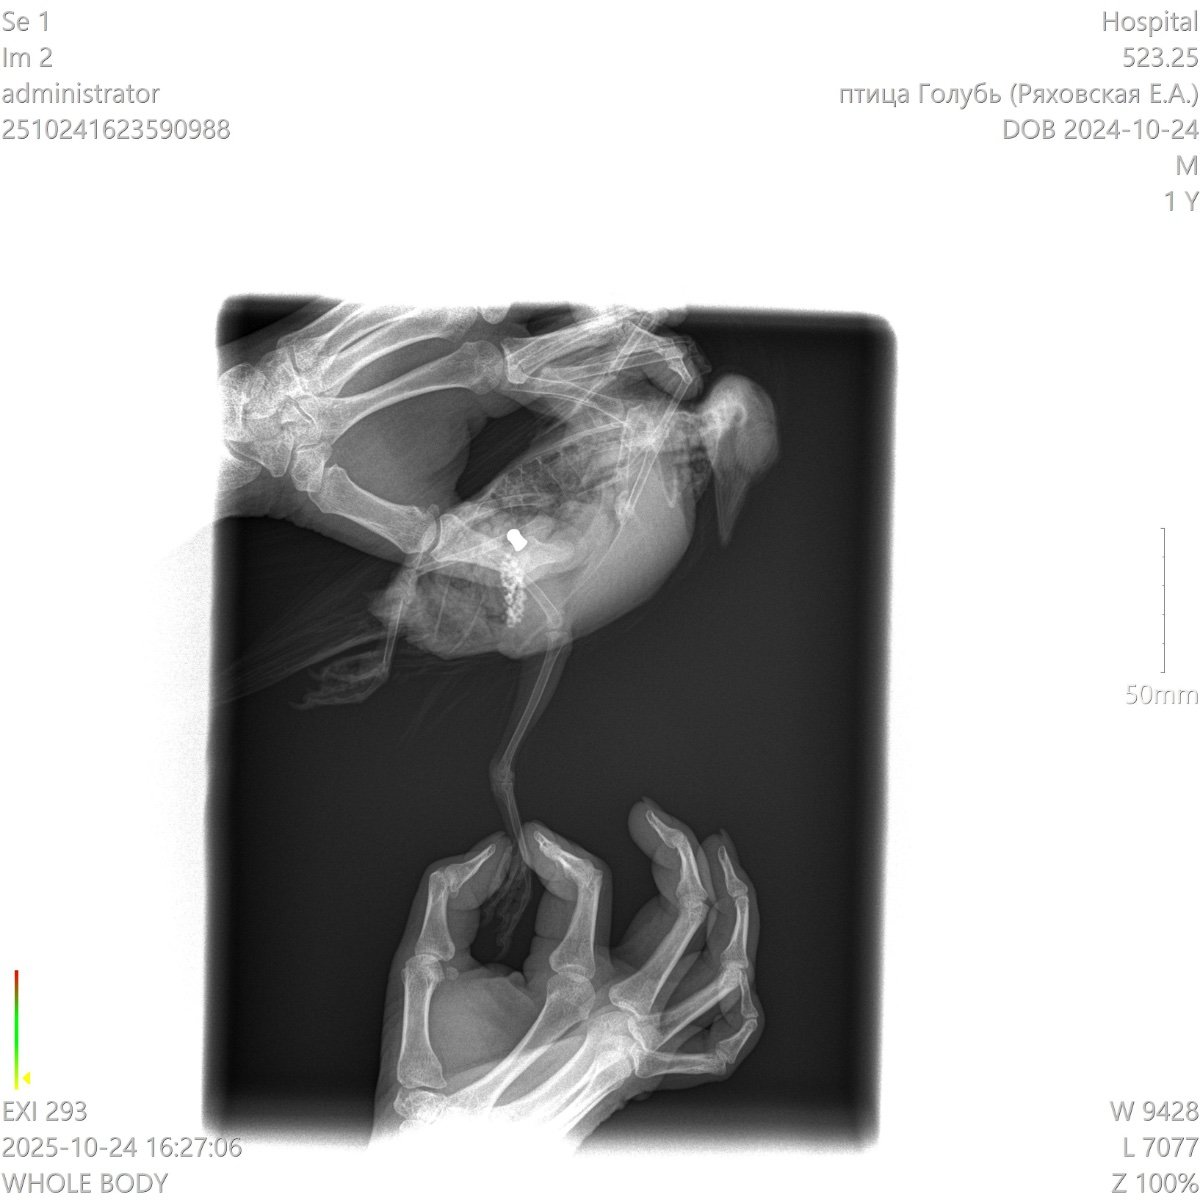

У голубя не функционируют лапки

Добрый день! Подобрали голубя, не встает на лапки, у нас в городе нет орнитолога, ветеринар не может точно сказать что с птицей. Помет зеленого цвета, кушает хорошо, перья блестят, очень активный.

Может ли это быть перелом позвоночника? Если да, то есть ли у птицы шанс встать на лапы?

осмотрите поясницу под перьями нет ли синяка

в случае удара бампером по спине ноги отнимаются на несколько недель

ногами и хвостом шевелить может?